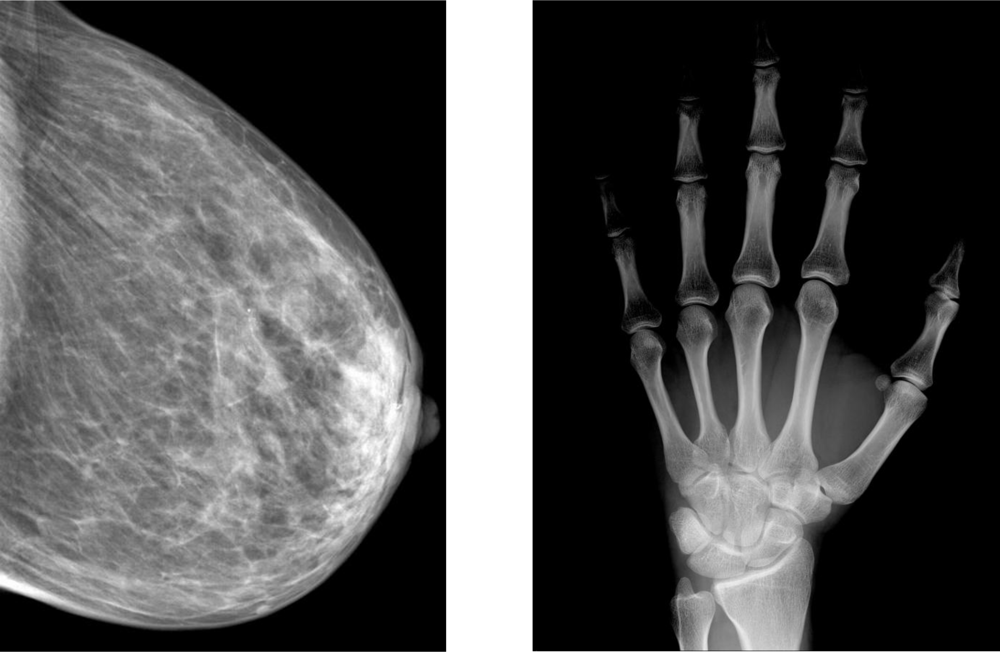

Figure 3 shows a stabilized a-Se based FPXI (AXS-2430) for mammography that has been developed and marketed by Anrad. Figure 4 shows two examples of x-ray images taken by an a-Se FPXI: a breast and a hand. The particular FPXI in Figure 3 has a field of view of 24 cm × 30 cm and the pixel pitch is 85 μm. There are 2,816 × 3,584 pixels in the sensor, each pixel being essentially an x-ray detector that, as mentioned above, generates an amount of charge that is proportional to the incident x-ray dose. Because such sensors can capture and process images in a very short time, they can be used in tomosynthesis (the three dimensional reconstruction of an object using several x-ray images taken at different angles), which is a distinct advantage. For example, the mammographic detector in Figure 3 can acquire up to 3 frames per second in the breast tomosynthesis mode without the need for binning (connecting two or more pixels in parallel to increase the signal). In tomosythesis, the detector captures N images at different angular views with the total exposure kept about the same to avoid increasing the patient dose. Each frame therefore has 1/N amount of exposure, that is, fewer photons than in conventional mammographic imaging. To make up for the reduced number of photons, the pixels can be binned at the expense of resolution. The choice between binning vs. high resolution is obviously quite important, and depends on a number of factors as discussed by Zhao [61]. It should be remarked that the a-Se detector marketed by Hologic has a different structure than that shown in Figure 2; an insulating organic layer is used between the positive electrode and a-Se to block hole injection and reduce the dark current. Hologic’s recently patented detector structure is capable of both static imaging and tomosynthesis [62].